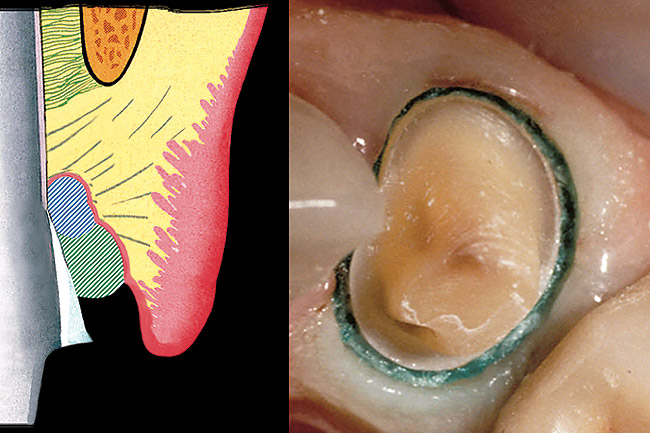

Figure 1  View of 4 porcelain veneer preparations with the margins placed at the level of tissue.

Figure 1

Figure 2  Note the invisibility of the marginal line in the completed veneers, even though the margin has not been carried below tissue.

Figure 2

A clinician is faced with 3 options for for margin placement when considering an anterior esthetic restoration: supragingival, equigingival (ie, even with tissue), and subgingival.1 The supragingival or equigingival margin will have the least impact on the periodontium and, classically, was only used in nonesthetic areas because of the stark contrast in color and opacity of traditional restorative materials. With the advent of adhesive dentistry, resin cements, and more translucent restorative materials, the ability to place supragingival or equigingival margins even in esthetic areas is now a reality (Figure 1 and Figure 2). The primary requirement of a material to enable its use in esthetic areas supra- or equigingivally is a high level of cervical translucence. Materials such as feldspathic porcelain, as well as pressable ceramics, meet this requirement. Consequently, whenever possible, these restorations should be chosen not just for their esthetic advantages, but for their favorable periodontal impact as well. The greatest biologic risk occurs when placing subgingival margins.2